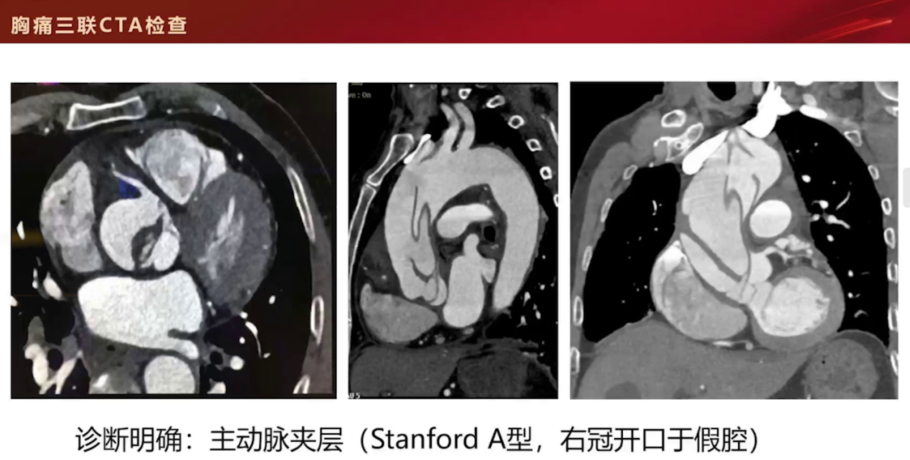

胸痛三联CTA结果:

冠状动脉:右冠、左前降支、回旋支可见多发钙化斑、混合斑及非钙化斑,管腔轻至中度狭窄;心肌密度均匀。

肺动脉:主干及分支形态、走行正常,未见栓塞征象。

主动脉:升主动脉管腔增宽,主动脉瓣上方可见破口及线状内膜瓣,形成真假两腔(假腔大、密度低,其内见血栓形成;真腔小)。左冠状动脉起自真腔,右冠状动脉起自假腔。

1.主动脉夹层(右冠开口于假腔)

2.冠状动脉粥样硬化